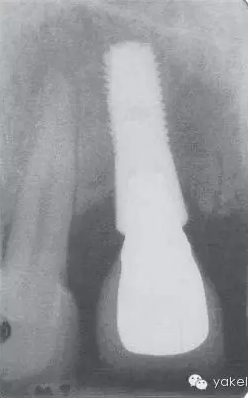

該患者上頜牙列缺失行種植修復(fù),種植體周圍存在嚴(yán)重骨喪失,造成了嚴(yán)重的美學(xué)問題(圖.14A)。大多數(shù)種植體周圍支持骨吸收達(dá)1/2義齒修復(fù)。

圖.14 (A)上頜牙列缺失行種植修復(fù),種植體發(fā)生廣泛的種植體周圍炎。(B)影像學(xué)檢查進(jìn)一步證實(shí)UL4、UL5種植體已脫落。